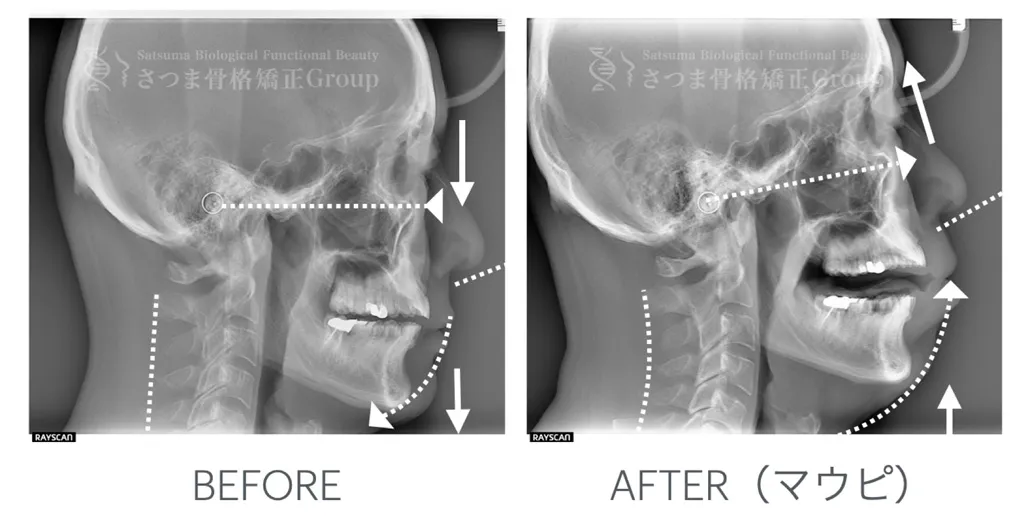

顎の回転中心から上向き(前方回転)変える事で、3つの反重力的機能美の連鎖が起こる

顎関節の回転中心を上方へ導くことで、蝶形骨と上顎複合体の位置関係が再整列し、頭蓋顔面構造のバランスが最適化されます。これにより、上顎の支持力が回復し、中顔面のリフトアップ、顔面比率の改善、左右対称性の向上といった審美的変化が連鎖的に生じます。

さらに、この整った構造を安定維持し、リモデリングを促進するためには、小顔マウスピースを用いたエクササイズによって、顎関節と咀嚼筋群に適切な物理的刺激を継続的に与えることが重要です。